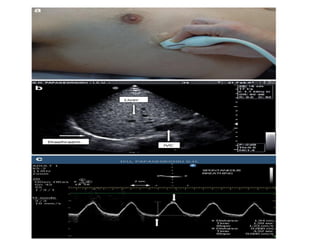

Tissue pattern representative of Alveolar

Consolidation

Presence of hyperechoic punctiform

imagesrepresentative of air bronchograms

Pleural

effusion

Lower lobe

Tissue pattern representativeof Alveolar Consolidation Presence of hyperechoic punctiform imagesrepresentative of air bronchograms Pleural effusion Lower lobe